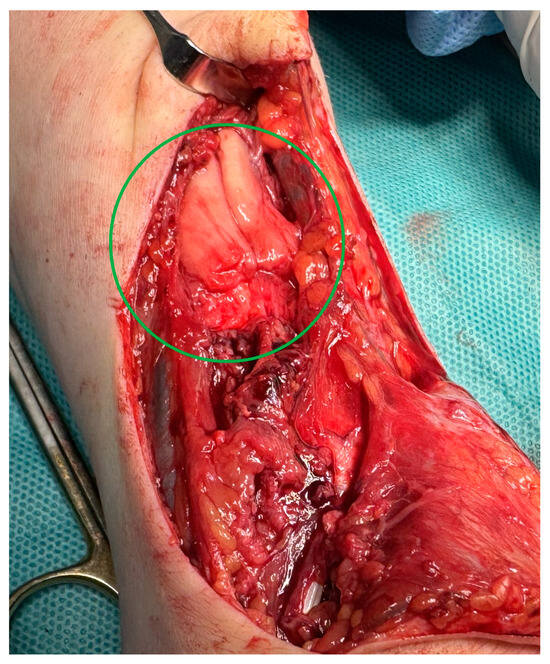

Figure 3.

An intraoperative image showing the proximal ends of the damaged ECRL and ECRB tendon formed a common scar.

After debriding ends, the tendon deficit was estimated at 4 cm for ECRB and 5 cm for ECRL. After removing the scar band around the damaged APL tendon and mobilizing the ends, the tendon defect was estimated at 4 cm. Partial EPB damage did not require repair. The extensor retinaculum was damaged for the second and third compartments covered by scar tissue. The first compartment was preserved, including EPB, but with a loss of APL. Due to the long-lasting forced positioning of the hand and partial damage to the extensor retinaculum, ulnar tucking of the undamaged extensor apparatus of the hand was found. The palmaris longus (PL) tendon, with a total length of 17 cm, was collected from separate microincisions on the palmar surface using a dedicated harvester. After surgical debridement, the graft was divided into three parts with lengths of 2 × 5 cm and 1 × 6 cm, respectively. The grafts prepared were then sewn into the distal ends of ECRL, ECRB, and APL using the Pulvertaft technique. The scar at the level of the damaged retinaculum was debrided, followed by surgically reconstructing separate graft tunnels. After placing the hand in an intermediate position, the PL grafts were sewn into the proximal extensor ends “overlapping” with a 1 cm margin (Figure 4). After the surgery, the limb was immobilized in a palmar splint in a dorsal flexion of approximately 20° for 2 weeks until the first follow-up. After confirming proper wound healing, the sutures were removed, and the splint was modified to ensure a neutral hand position. Two weeks after surgery, we started passive wrist and thumb motion to ensure the gliding of the reconstructed tendons and avoid potential adhesions. Four weeks after the procedure, the plaster splint was changed to an orthosis, holding the wrist in a neutral position, and actively mediated extension was added into the rehabilitation protocol. In Figure 5, we have shown longitudinal ultrasound sections of the reconstructed tendons, confirming the efficacy of the distal Pulvertaft sutures with no splitting of the tendon ends. Six weeks after surgery, the patient began intensive rehabilitation under the supervision of the outpatient rehabilitation department. Twelve weeks after the extensor reconstruction, during a follow-up, active wrist extension and radial wrist deviation were preserved with a deficit of 20° and 10°, respectively. The thumb abduction was maintained in the full range but with a mild limitation of thumb opposition. The patient was referred to additional rehabilitation combined with manual therapy and scar tissue mobilization. At the follow-up visit, 6 months after the reconstructive surgery, the patient presented a full range of motion: video documentation (Supplementary Materials).